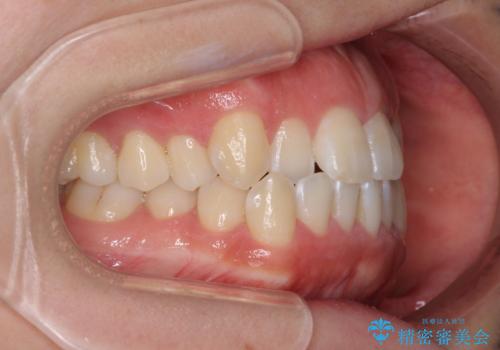

- 口元の突出感と口の閉じにくさ、前歯のデコボコを気にして来院された患者様です。

上下左右第一小臼歯4本を抜歯し、ワイヤー装置にて口元を引っ込めるよう矯正治療を行うこととしました。

骨格的に下顎骨が前方位にあるため、口元の突出感改善には限界があると思われましたが、唇の閉じにくさが改善するほど引っ込めることができました。